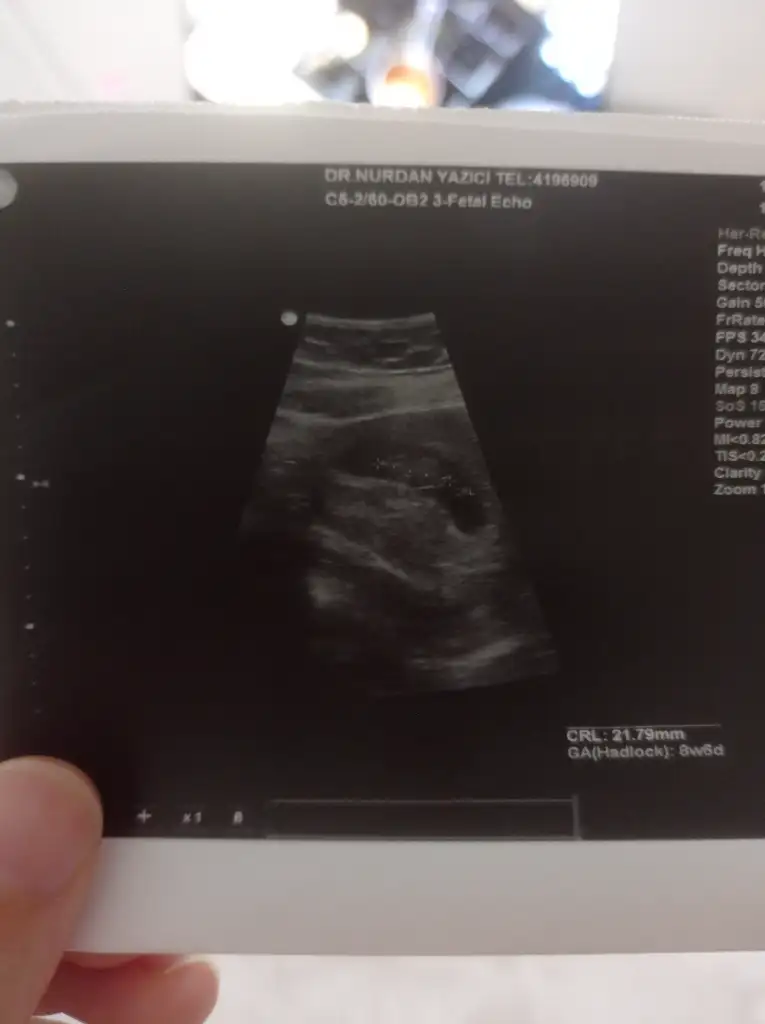

8+6 karından ultrasonla çekildi cinsiyet tahmini yapabilecek var mı acaba

Eklentiler

• IMG_20250616_223900.webp

IMG_20250616_223900.webp

11,8 KB · Görüntüleme: 62